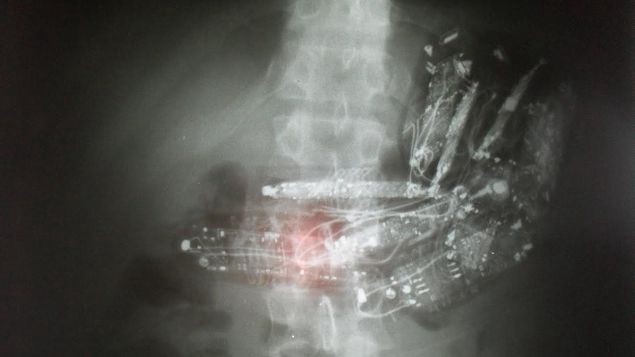

Al tercer preso, al pasar por los rayos X, se le descubrieron diez minicelulares con auriculares en su estómago y fue sometido a una operación para retirarle todos los aparatos.